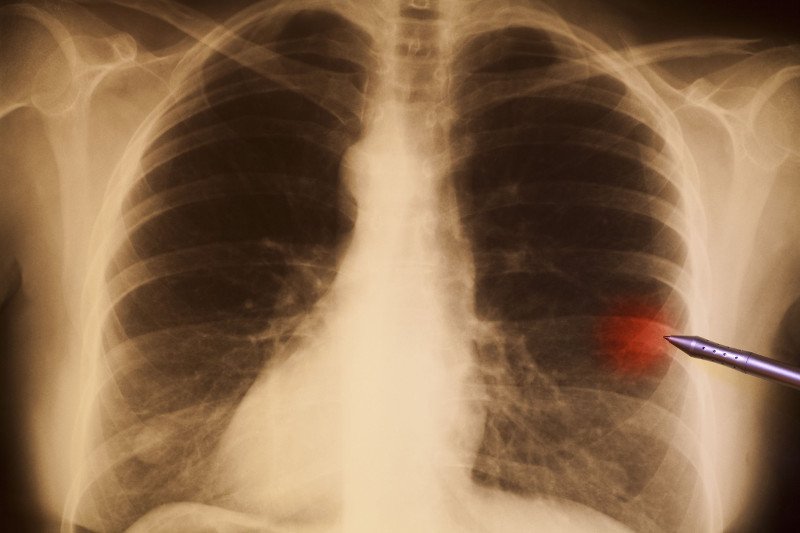

47-latek zmagał się z uporczywym kaszlem. Ponieważ był nałogowym palaczem, udał się do lekarza, by znaleźć powód złego samopoczucia. Po wykonaniu prześwietlenia odkryto dziwny cień na jednym z płatów. Niestety diagnoza wstrząsnęła mężczyzną. Rak płuc zabrzmiał jak wyrok.

Mężczyznę skierowano na dodatkowe badania. W czasie bronchoskopii, czyli wziernikowego badania dróg oddechowych znaleziono rzeczywistą przyczynę złego samopoczucia pacjenta. Trudno było powstrzymać śmiech i ukryć zdziwienie, gdy odkryto w drogach oddechowych zabawkę Playmobile, którą połknął 40 lat wcześniej. Mężczyzna przyznał, że gdy był małym chłopcem, zdarzało mu się czasem połykać drobne przedmioty, nigdy jednak z tego powodu nie miał problemów medycznych.

Lekarze byli zaskoczeni, że ciało obce nie dawało żadnych poważnych oznak przez tyle lat. W czasie operacji usunięto zbędny przedmiot, a był nim mały pachołek drogowy. Dziś może on być niezwykłą pamiątką dla mężczyzny, który na szczęście okazał się zupełnie zdrowy. Może jednak powinien przestać palić i wziąć na poważnie ostrzeżenie.